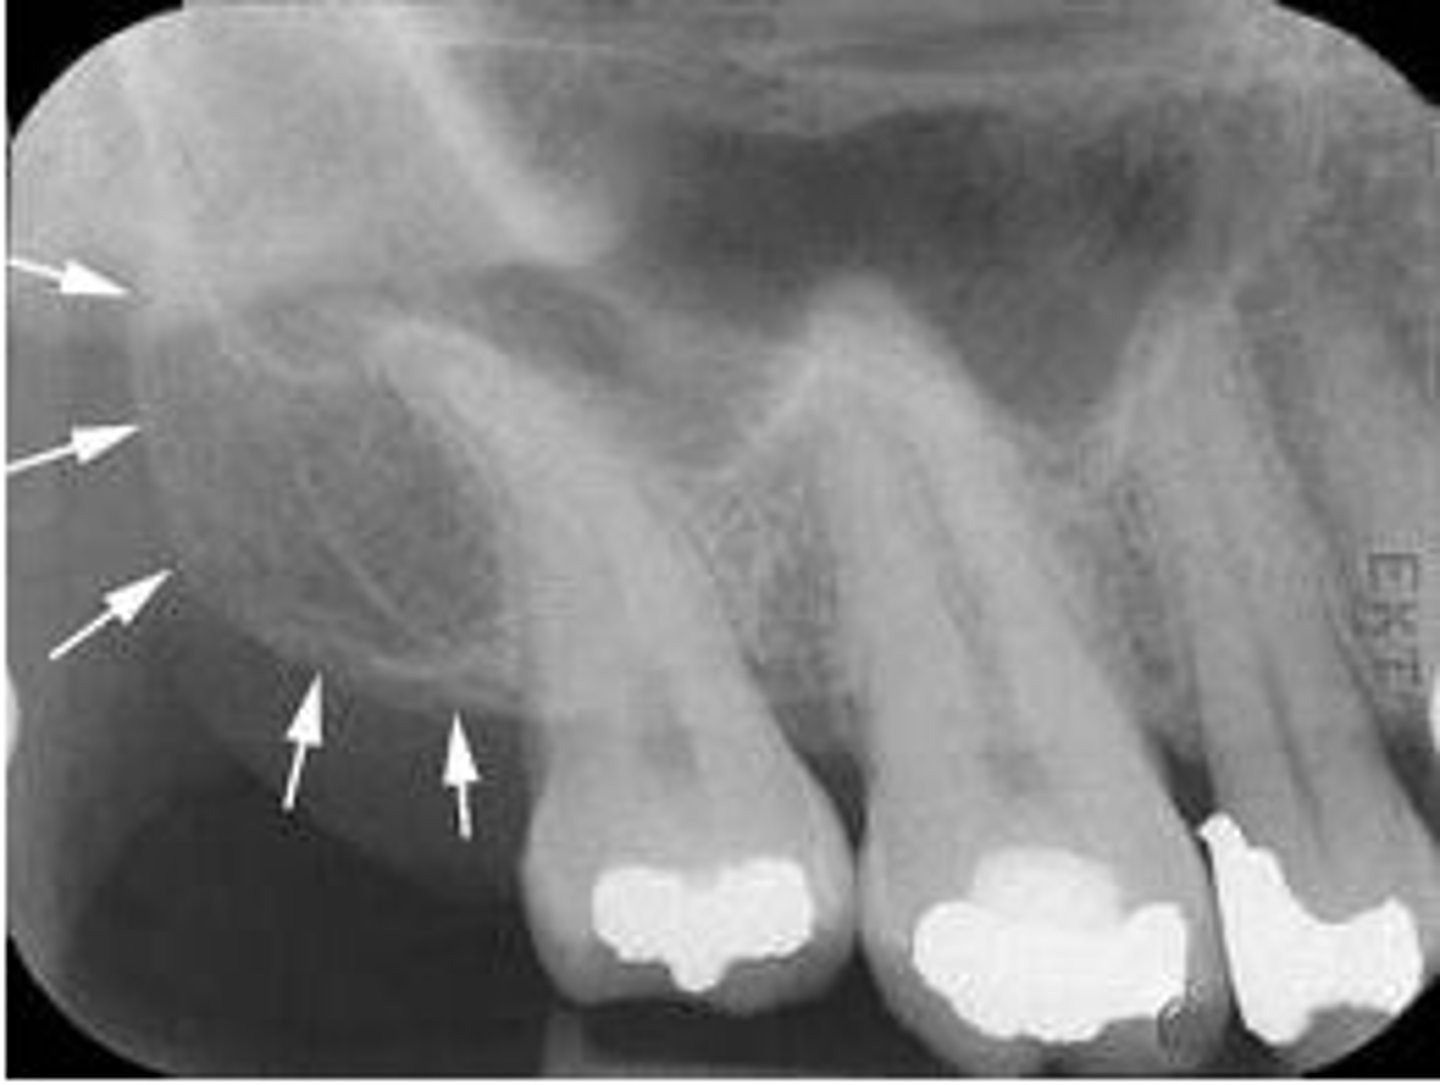

submandibular gland fossa

rounded area of bone

less dense

space for submandibular salivary gland